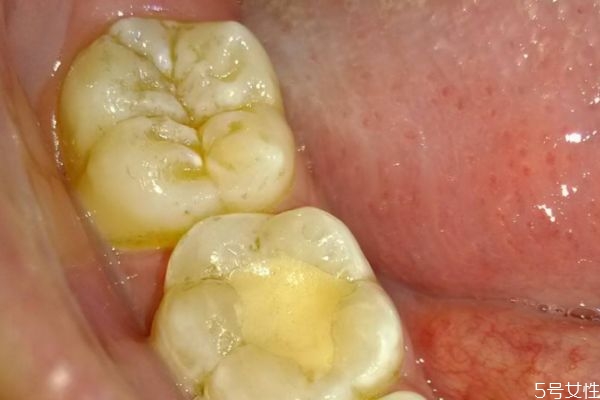

牙齦腫痛的絕大部分原因,還是牙結(jié)石或者說是軟垢的刺激。牙齒表面不干凈,軟垢以及結(jié)石的堆積,就會刺激這個牙齦,刺激牙齦的血管擴張,然后牙齦就會紅腫出現(xiàn)疼痛,經(jīng)常發(fā)生牙齦腫痛,必須要到醫(yī)院來進行檢查。針對具體的情況,進行具體的處理。如果是軟垢或者結(jié)石的刺激影響,那么主要的治療方法,還是進行洗牙潔牙,或者說是超聲波潔治,如果長期出現(xiàn)牙齦腫痛,不處理的話病人一般會自己,第一次自己很難受,然后第二呢牙齦出血,也會對你的社交造成一些困擾。第三長期的牙齦腫痛,牙齒的炎癥得不到有效的控制,會使牙槽骨以及牙齦萎縮,那么牙齒會松動,牙齒松動以后,一般來說絕大部分情況,沒有辦法再恢復正常,會造成牙齒脫落。

牙齦腫的危害性是特別嚴重的,對于患者的牙齦健康損害嚴重,病發(fā)期間給患者帶來了困擾,甚至會干擾到工作以及生活,提醒各位朋友需要將牙齦腫了解透徹,平時的生活中多了解相關(guān)的誘發(fā)起因,生活中誘發(fā)牙齦腫的起因特別的復雜,主要包括牙周膿腫、牙齦膿腫、智齒冠周炎、根尖周炎等,這是都是常見的病因,很多人會因為這些病癥而出現(xiàn)牙齦腫痛的癥狀,從而侵害了牙齒及牙齦部位的健康。如果患者自身存在牙齦或者是牙周組織方面的慢性炎癥,特別是患者的機體抵抗力嚴重下降、天氣干燥、進食辛辣及刺激性嚴重的食物時,都會導致原有的慢性炎癥產(chǎn)生急性的發(fā)作,繼而誘發(fā)了牙齦腫痛的癥狀,傷害了患者的牙齦健康,為此朋友們要注意口腔的衛(wèi)生,正確的刷牙,還要注意提早做一些牙齦腫痛的預防工作,這樣才能減輕牙齦腫的病發(fā)率,從而保護了人們的牙齦健康,遠離了疾病的困擾和損害。